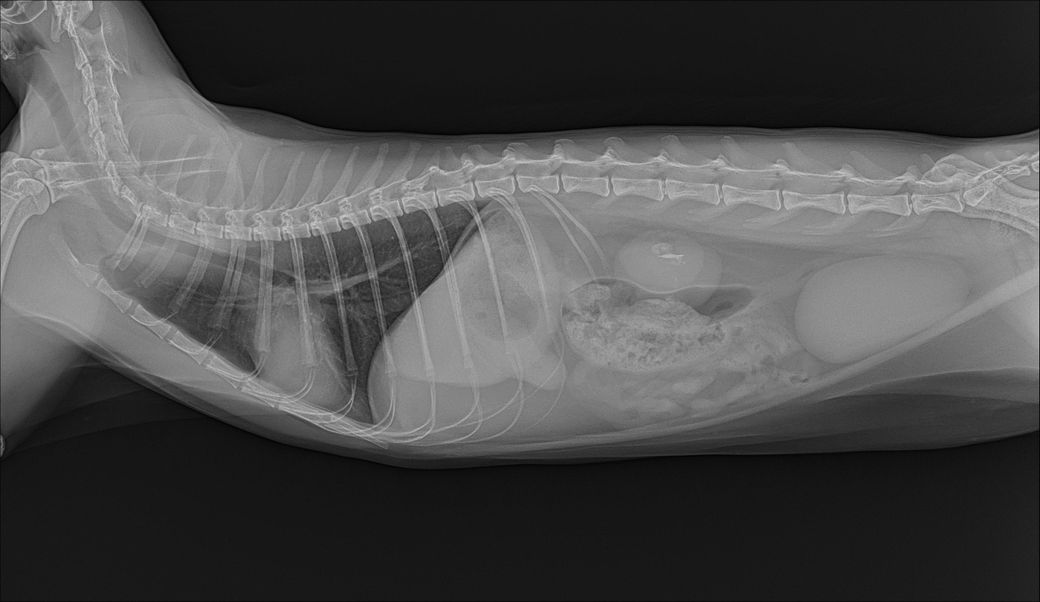

3살 암컷고양이 엑스레이 촬영에서 작은 신장결석이 발견됐는데 인흡작제를 먹이는게 좋을까요

나중에 수술하지 않게 미리 뭔가 해줄수있는건 없을까요